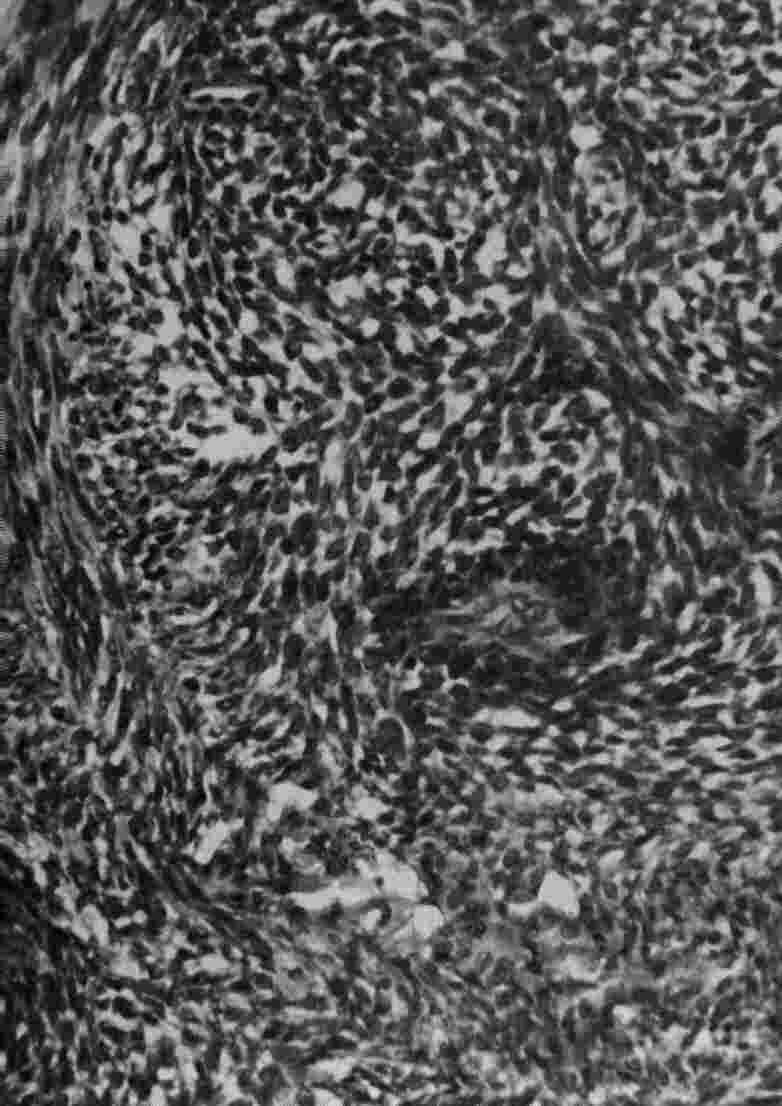

The cells in this tumor have an epithelial like quality, and are arranged in a palisading or glandular pattern, surrounded by a fibrous stroma.

Histology shows a combination of spindle cells and epithelial cells, with the palisading effect .